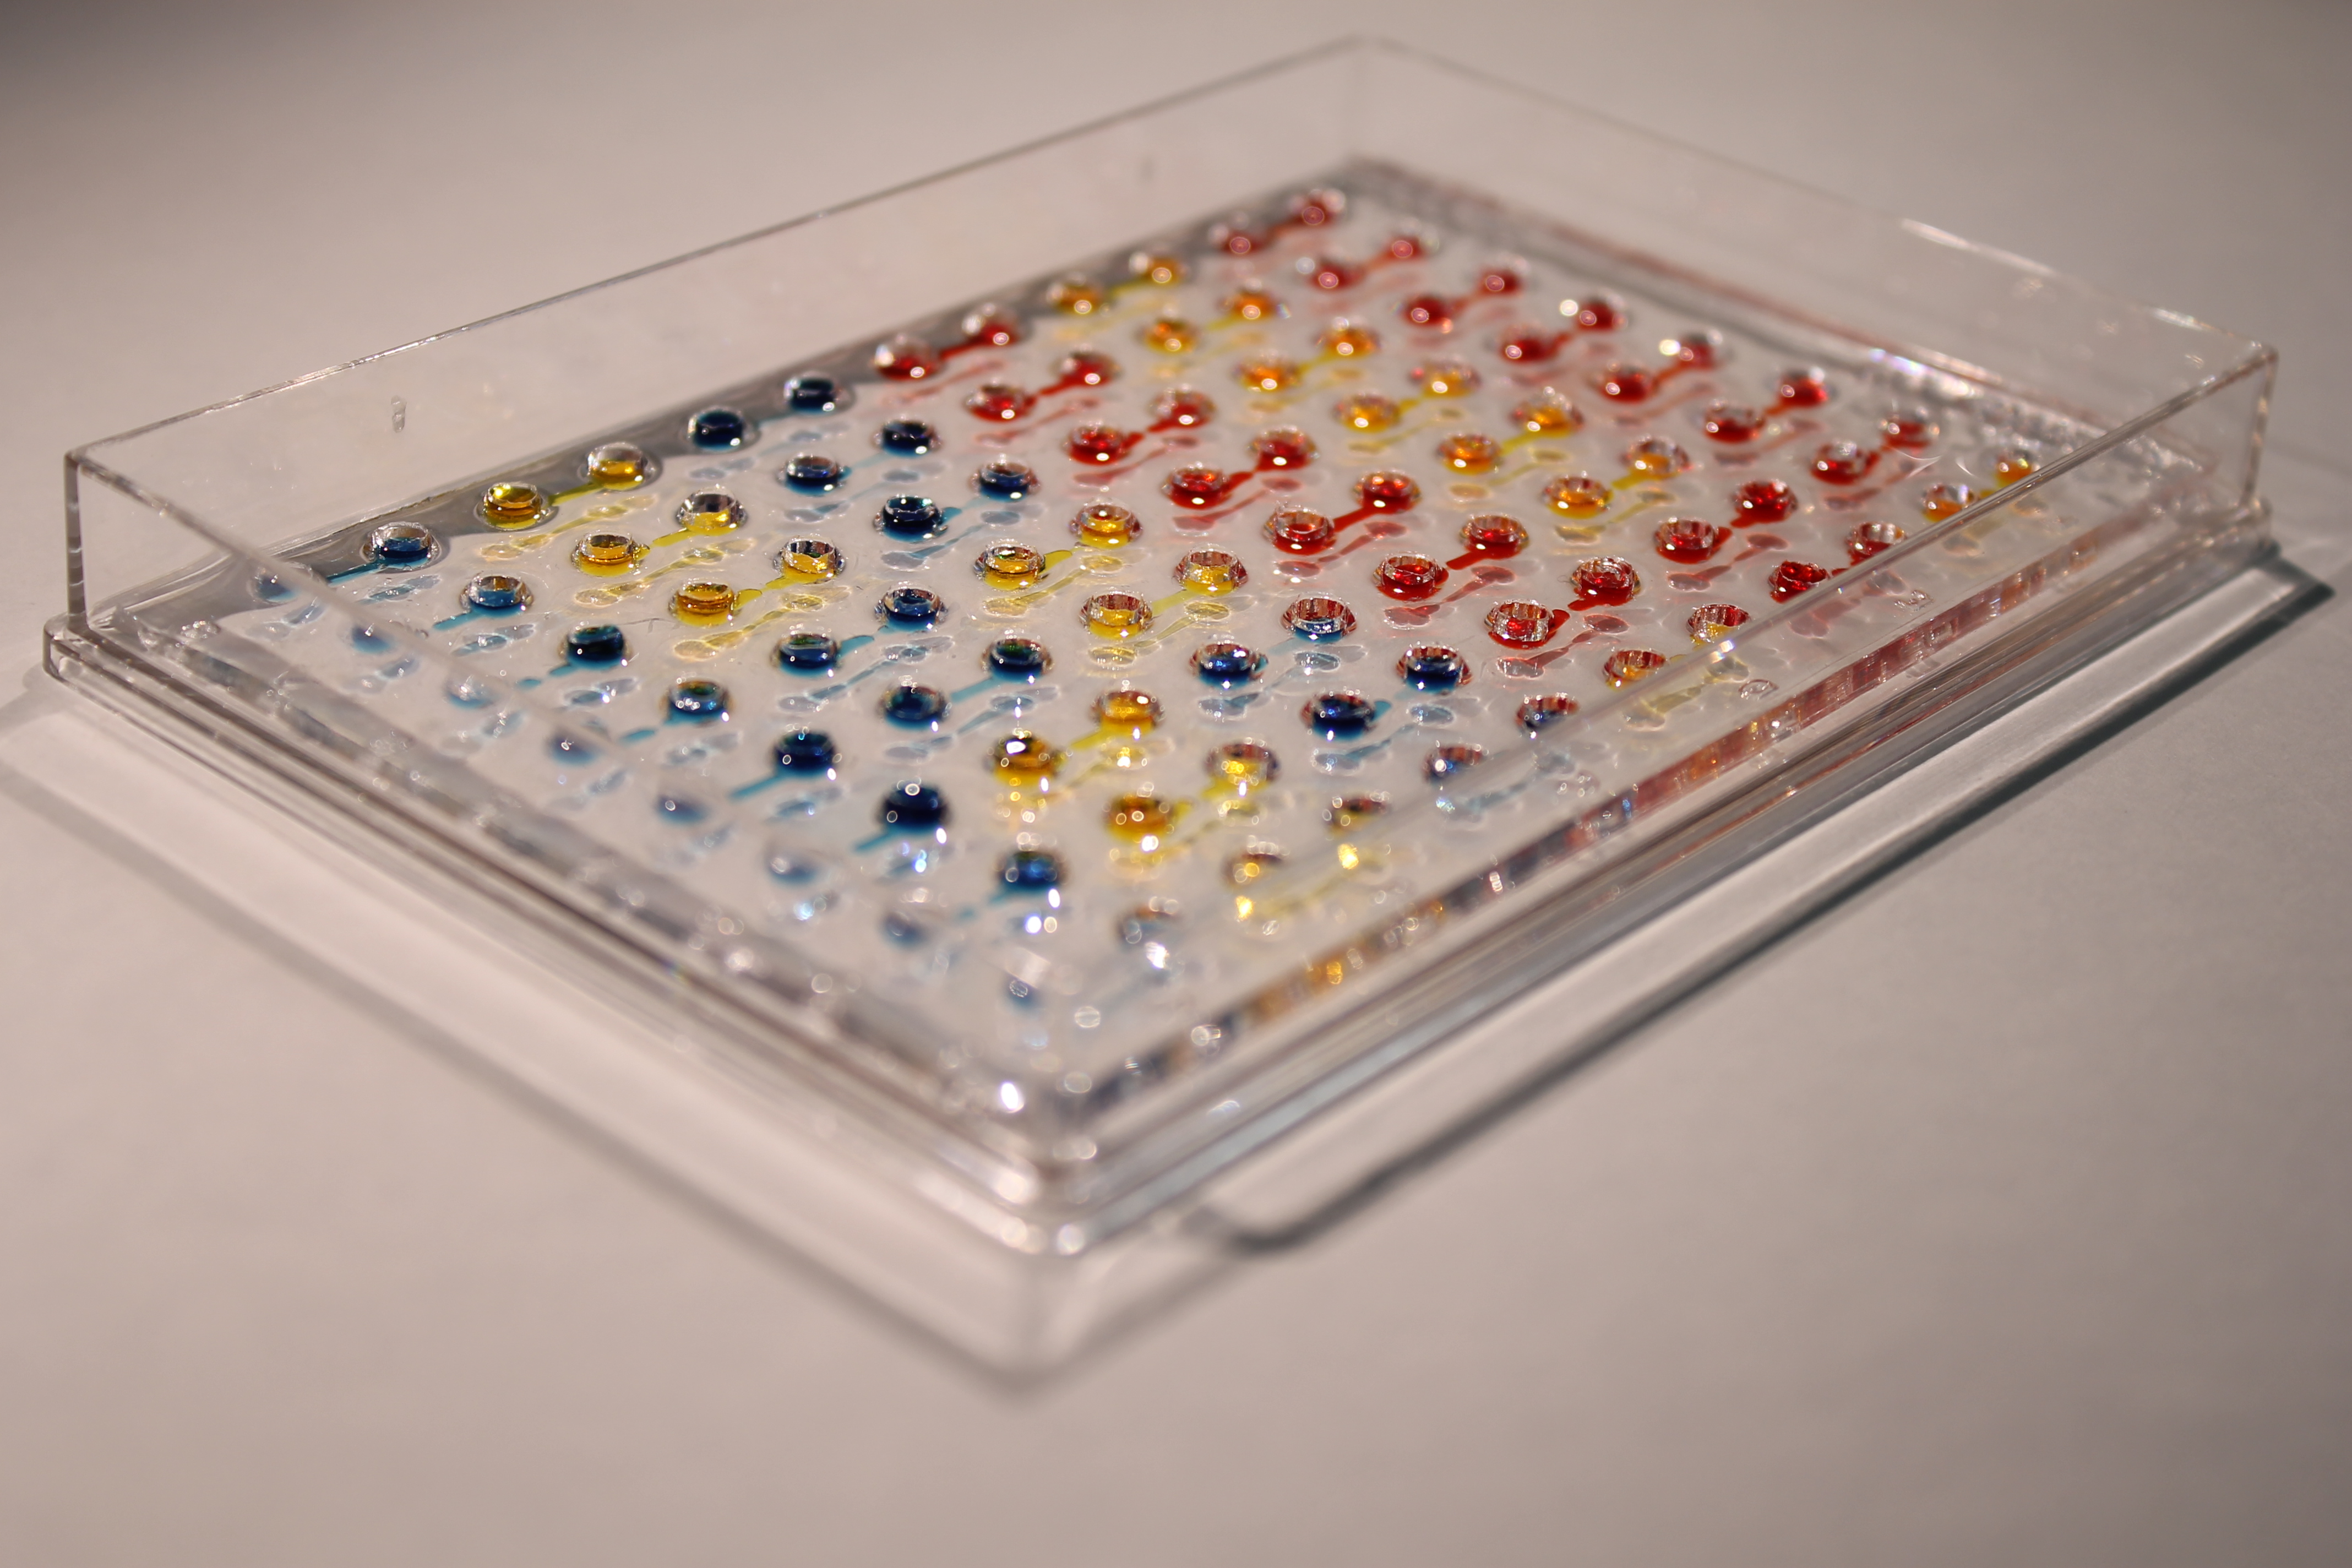

Pharma requires reproducible, high-throughput human tissue assays that integrate with existing R&D workflows and regulatory needs.

Miniaturized human liver, heart, and other organ models for high-throughput screening.

Scalable drug testing to predict efficacy and toxicity with greater human relevance.

Our patented innovative human-centric platform transforms how drugs are tested, delivering accurate predictions earlier, reducing costs, and fast-tracking approvals. Here’s how we give our customers the edge:

High-throughput tissue plates enable rapid, reproducible assays that plug into existing R&D pipelines, shortening timelines, lowering per-assay cost, and accelerating go/no-go decisions.